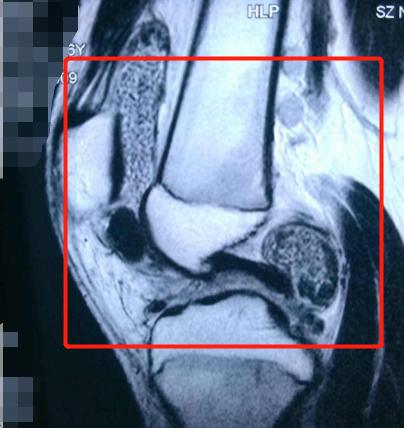

可见关节软组织病变

可见薄薄的滑膜